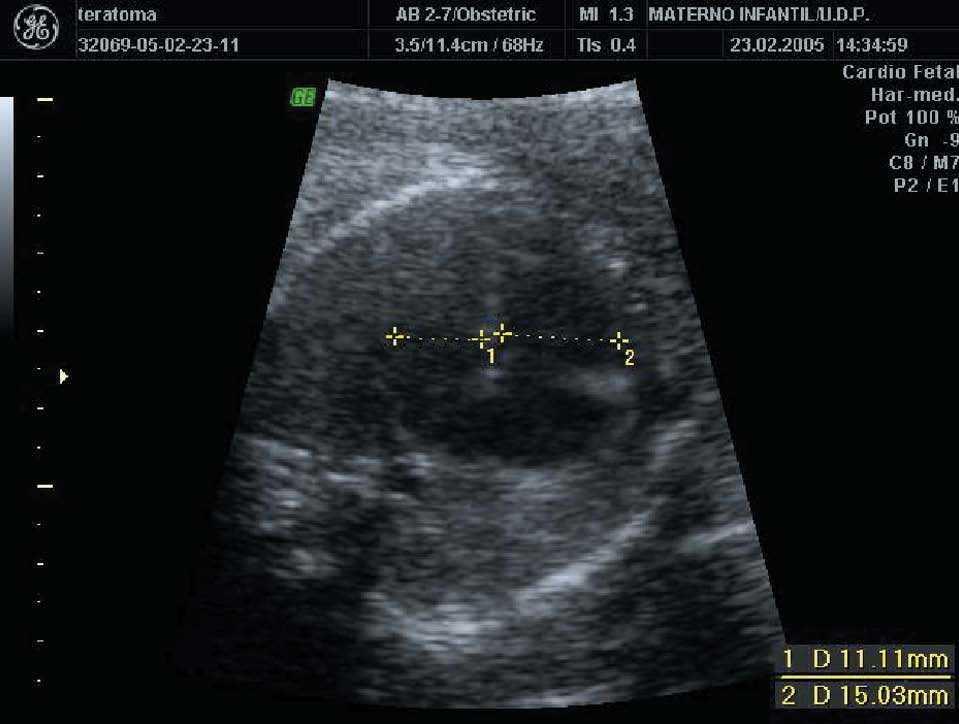

En la siguiente exploración ecográfica, en la semana 25 + 3, se observó un crecimiento de la tumoración con diámetros de 91 × 97 × 91 mm (fig. 3). No se observaban signos de sobrecarga cardíaca, y el Doppler del ductus venoso y la arteria cerebral media eran normales. Como hallazgo adicional a la ecografía anterior, se constató una pielectasia bilateral de 9 mm y un hidramnios (ILA 28) (fig. 4).

Figura 4. Ecografía realizada en la semana 25, donde se aprecia una pielectasia bilateral de unos 9 mm.